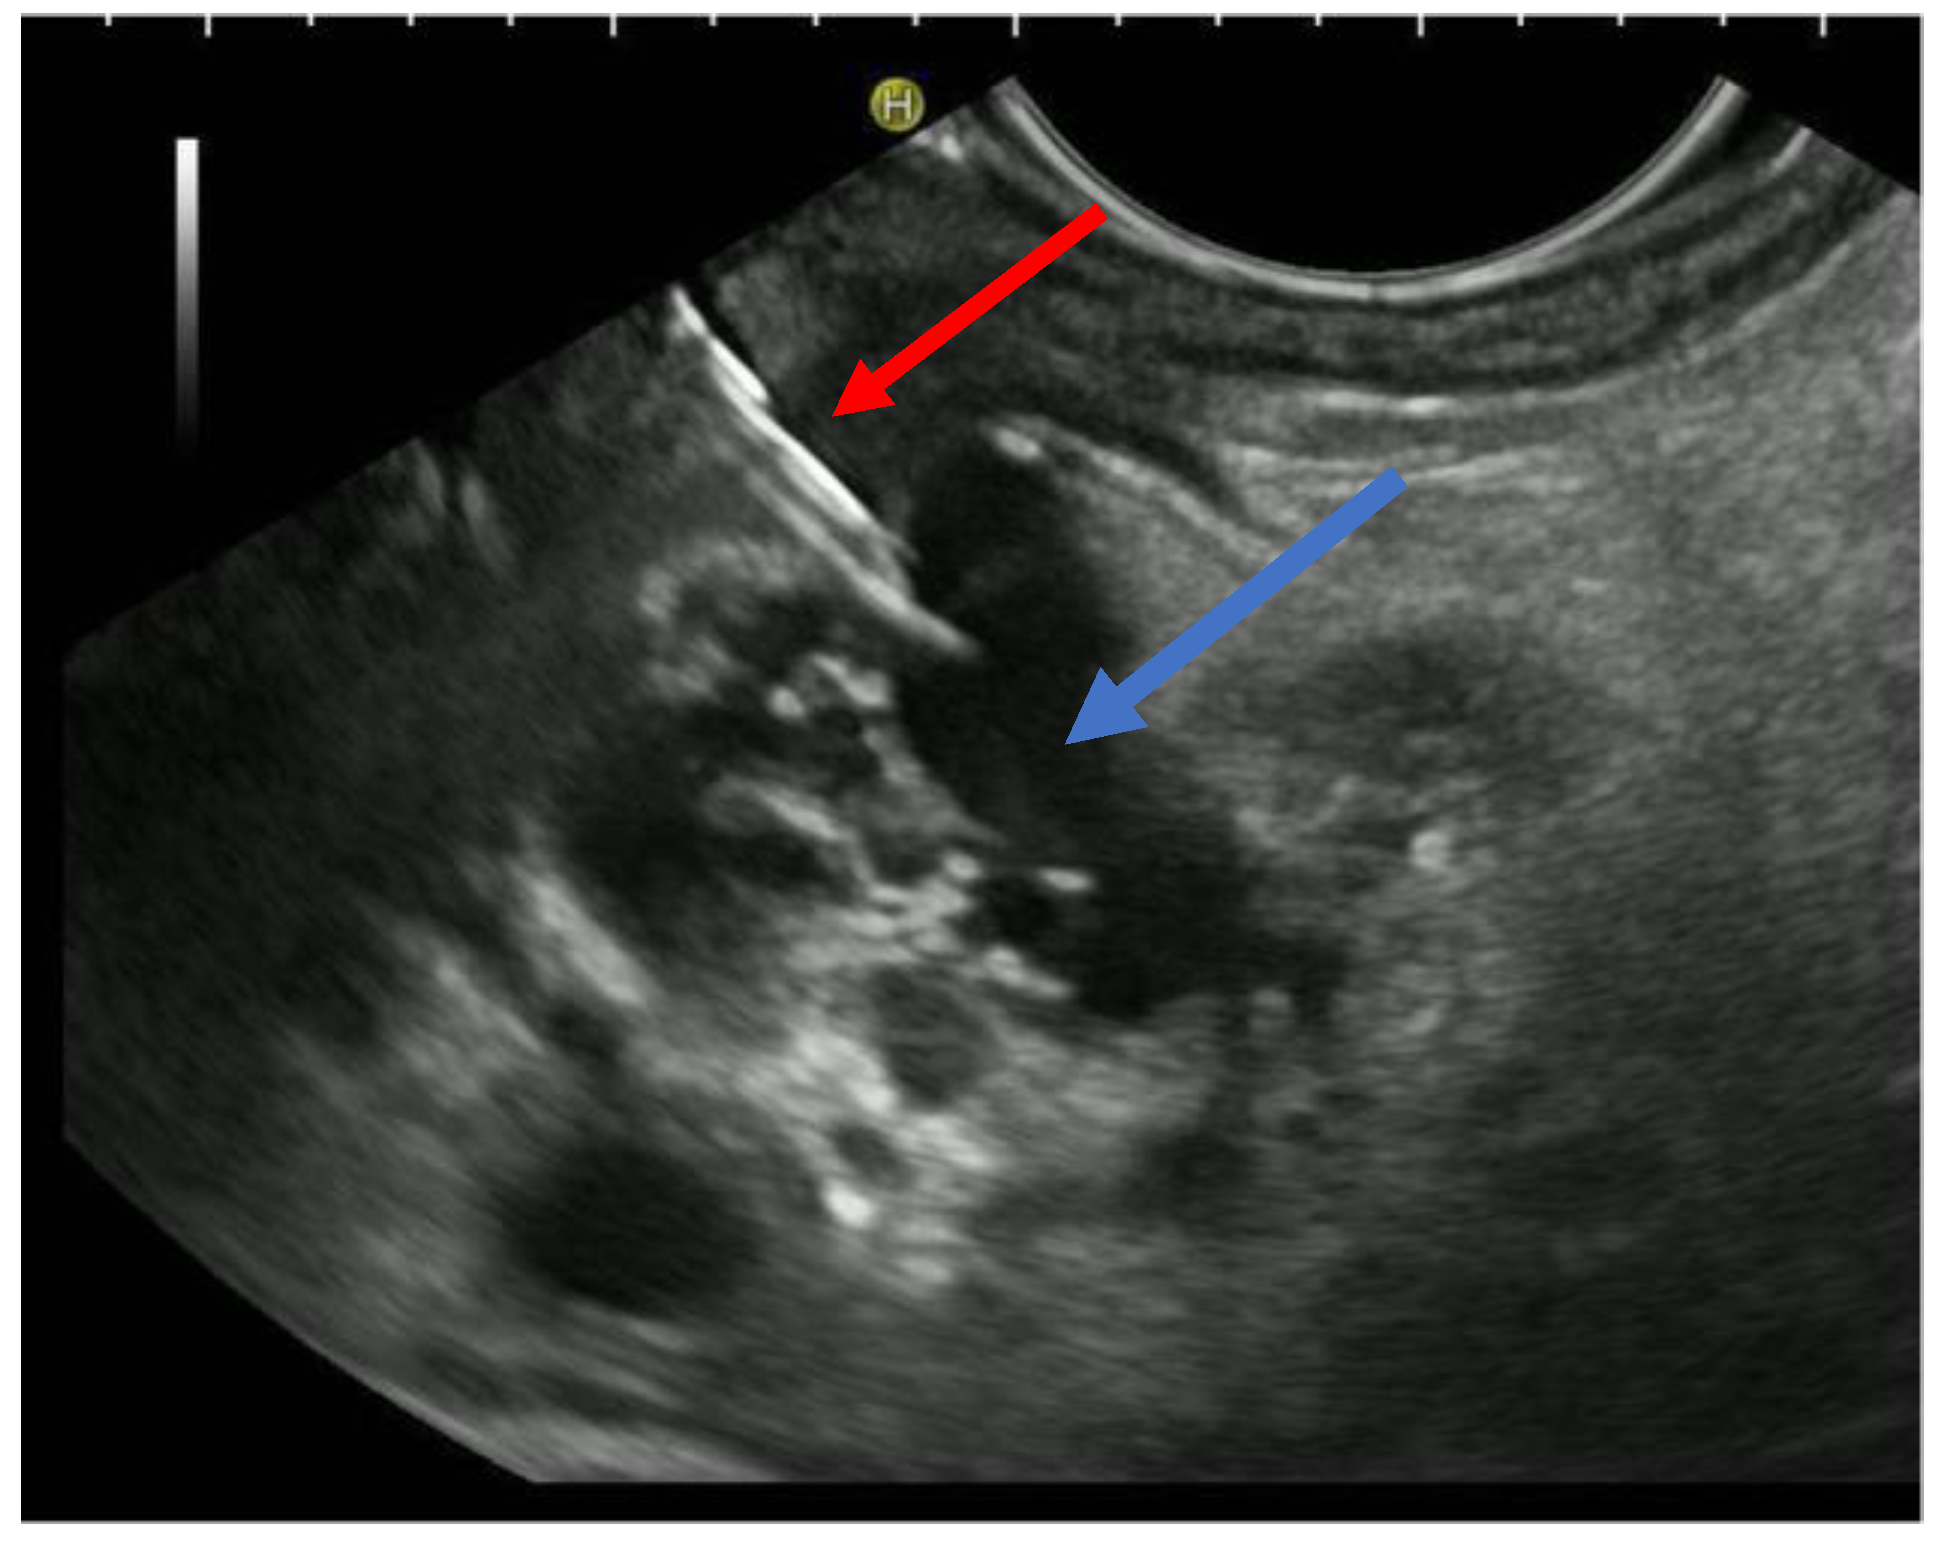

The patient is positioned prone on an X-ray fluoroscopy table and undergoes endoscopic ultrasound (EUS) using a therapeutic longitudinal scanner (e.g., EG 3270 UK, Hitachi Ultraschall, Berlin, Germany; GF-UCT 180, Olympus, Hamburg, Germany; Fuji EG-580UT2, Tokyo, Japan) following unsuccessful conventional ERP, with peri-interventional antibiotic administration i. v. (2 g ceftriaxone or 4 g tazobactam). Once the pancreatic duct is identified, a 19-G needle (Boston Scientific, Ratingen, Germany; Olympus, Hamburg, Germany) is used to puncture it in the direction of the anastomosis or papilla. Pancreatic juice is aspirated and sent for microbiological and cytological examination. Subsequently, the pancreatic duct is visualized via X-ray fluoroscopy following the instillation of the contrast medium (Figure 1 and Figure 2—selected from the clinical picture library of the reporting Dept. of Gastroenterology, Hepatology and General Internal Medicine as all the following figures).

Figure 1. Intraprocedural EUS image: Patients with remitting pancreatitis and dilated pancreatic duct; transgastric EUS-FNA (red arrow) of the dilated duct (blue arrows) and pancreatography (Figure 2), selected from the clinical picture library of the reporting Dept. of Gastroenterology, Hepatology and General Internal Medicine.